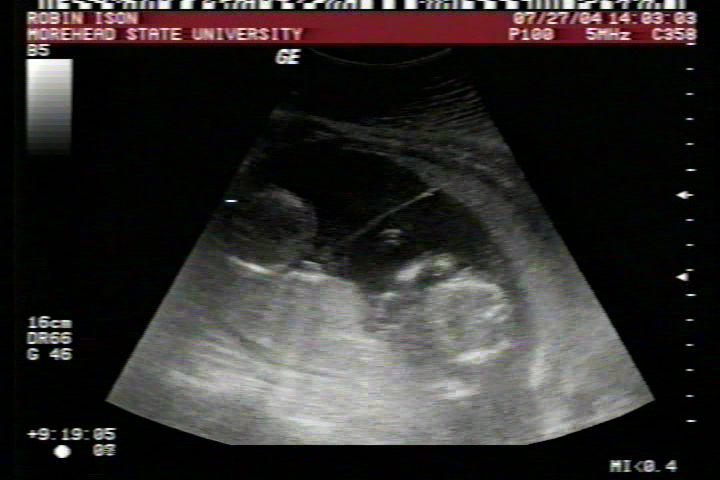

Pictures from Ultrasound at 17 weeks.